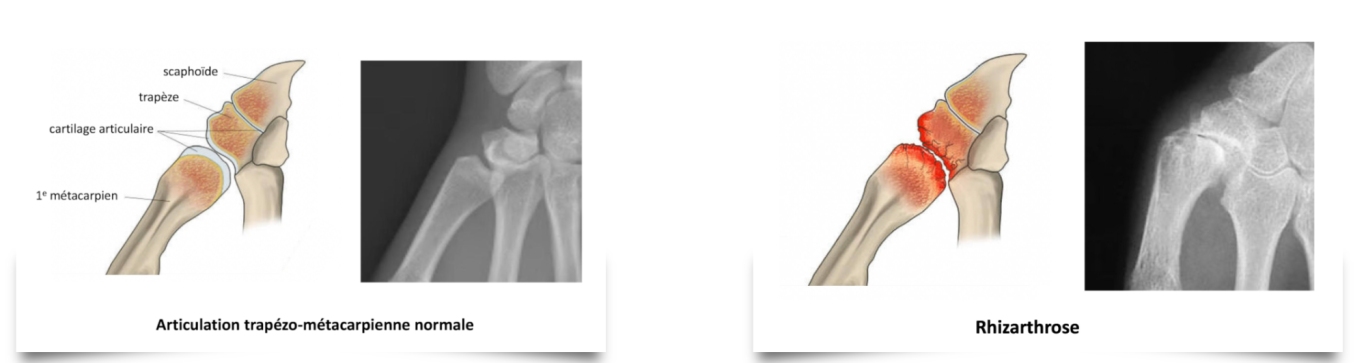

Rhizarthrose

DEFINITION : La rhizarthrose est l’arthrose de la base du pouce. C’est l’usure du cartilage entre le premier métacarpien et un os appelé trapèze. Cette usure progressive est relativement fréquente et touche surtout la femme (1 femme sur 6 après 60 ans). Elle touche souvent les 2 mains. Certaines formes sont héréditaires et peuvent alors apparaître avant la cinquantaine. Il n’y a pas de relations entre l’importance de l’atteinte sur les radios et l’importance de la gêne chez le patient.

SYMPTOMES : La douleur est le premier signe. Cette douleur apparaît lorsque l’on serre des objets avec le pouce. Simple gêne au début, elle peut devenir insupportable, le patient alors évite d’utiliser sa main. Les autres signes sont l’apparition d’une déformation avec impression de "bosse" à la base du pouce, perte de mobilité et baisse de force. La déformation peut après de nombreuses années devenir de plus en plus importante avec un pouce qui ne peut plus s’écarter de la paume et un retentissement sur l’articulation voisine du pouce : c’est le "pouce en Z".

EXAMENS : Les radios confirment le diagnostic et permettent au chirurgien d’apprécier l’importance de l’arthrose pour choisir la meilleure technique.